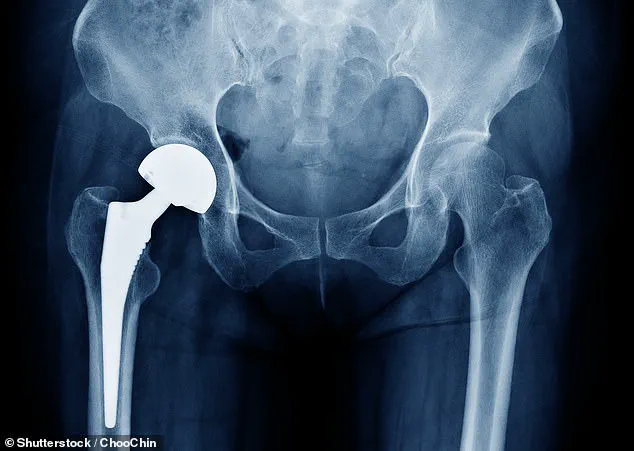

Hip replacement surgery is a common and generally effective intervention, with approximately 175,000 procedures performed annually in England, Scotland, and Wales.

The procedure typically involves replacing the damaged hip joint with a metal or ceramic ball and socket, and it is most frequently performed on patients aged 60 to 80.